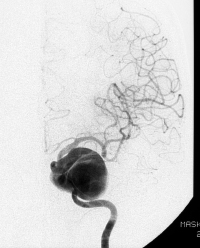

診断にはCTがたいへん有効で、発症24時間以内の診断率は92%であるとされています。 クモ膜下出血の診断がついたら我々は、患者さんに対する侵襲をなるべく避けて、血圧や呼吸を管理し、鎮静剤や鎮痛剤を使って再出血の危険性を下げるようにします。次いで原因となった脳動脈瘤を見つけて(カテーテル検査や3次元CTなどによって)これに対する治療を行います。

脳動脈瘤の治療としては脳動脈瘤クリッピング術と脳動脈瘤コイリング術の二つが代表的です。破れた脳動脈瘤の場所や形、大きさなどによって二つの方法を使い分けることが理想的です。 治療によって再出血を予防できたとしても、クモ膜下出血の治療はまだ終わりません。 少なくとも2~3週間はさまざまな合併症に対峙しなければなりません。 代表的な合併症が脳血管攣縮といって、脳の中の多くの動脈が細くなることによって脳への血の流れが悪くなるものです。これが高度になると脳梗塞を引き起こして意識障害や麻痺などを呈したり、ひどい時には亡くなってしまうこともあります。原因はまだ不明ですが脳血管の周りに存在する血液が悪さをするので、これをできるだけ洗い流すようにしたり、いくつかのお薬を使い、さらにはカテーテル治療によって対応しています。 また水頭症といって頭の中に水がたまってしまう合併症も時おり見られます。水頭症に対してはシャントという手術を行って治療することがあります。

脳動脈瘤の多くは嚢状といっていわゆるコブ状のものですが、その他に解離性動脈瘤といって動脈の壁が裂けてできたものがあり、やはりクモ膜下出血を引き起こすことがあります。解離性動脈瘤は嚢状動脈瘤よりもさらにクモ膜下出血急性期に再出血する危険性が高く、より迅速な治療が求められます。このタイプの動脈瘤に対しては、動脈の裂けた場所(解離部)を閉塞してしまう、トラッピングという治療が行われます。

我々は、内頚動脈に発生したこの解離性動脈瘤破裂によるクモ膜下出血に対して急性期に内頚動脈トラッピングを行い、さらに閉じた内頚動脈の代わりに腕の動脈(橈骨動脈)を移植する橈骨動脈(RA)グラフト術(radial artery graft)を行っています。このRAグラフト術は大型、巨大内頚動脈流の治療に用いることも多くあります。